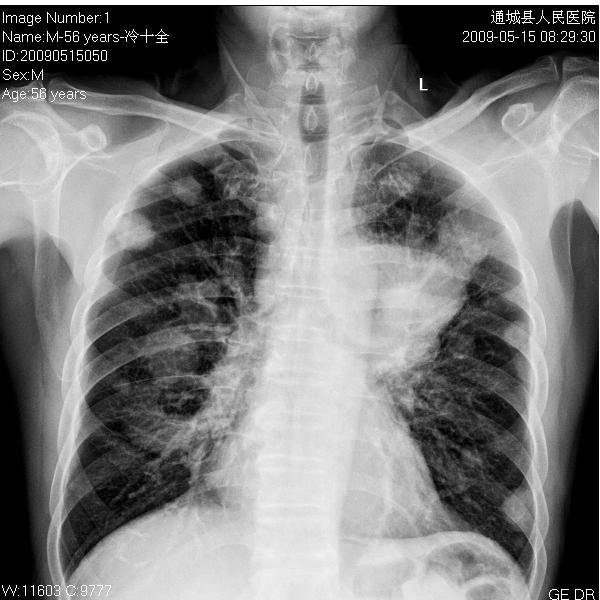

男性 56岁  咳嗽咳痰3-4天

多发转移瘤。查一下原发灶。

肺转移瘤

考虑左上肺中央型肺癌伴两肺转移。

左肺上叶中央型肺癌双肺转移。

典型----左上肺中央型肺癌伴节段性不张,两肺多发性转移。

左肺门区肿块较大,没有直接征象证明是中央型肺癌,谁能排除是周围型的呢?又没有照侧位。肺转移癌是比较确切的,原发灶就不能不好说了。

左侧中央型肺癌并双肺、肺门气管旁淋巴结转移.